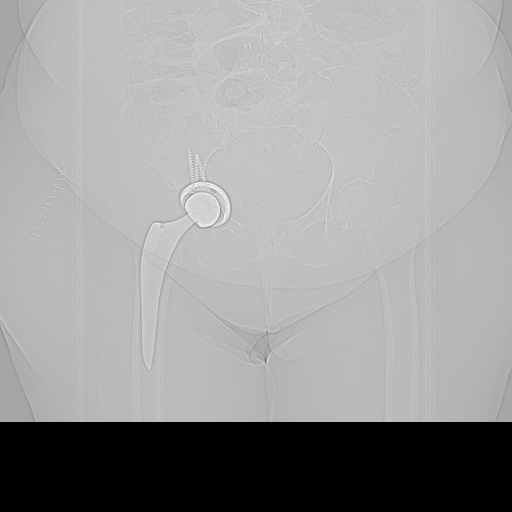

21.11.2025 - Luxiert

Röntgen November 2025

Prothesenkopf aus Pfanne luxiert

Akuter Befund: Hüftprothesen-Luxation

Vergleich der Röntgenbilder zeigt eine Luxation der Hüft-TEP rechts. Der Prothesenkopf ist aus der Pfanne ausgerenkt.

21.11.2025 - Luxation!

Becken 2025

Prothesenkopf luxiert nach medial/kaudal

Verlauf: Die Luxation/Pfannendislokation führte zur stationären Aufnahme im Universitätsklinikum Heidelberg (28.12.2025). Am 30.12.2025 wurde die TEP entfernt und ein Spacer implantiert. Infektnachweis: Enterococcus faecalis. Am 19.02.2026 wurde die neue Prothese erfolgreich eingebaut (stationär bis 05.03.2026). Komplikationsloser Verlauf, regelrechte Implantatlage im Röntgen. Entlassung mit 20kg Teillast, Amoxicillin für 6 Wochen. Wiedervorstellung am 09.04.2026.

21.11.2025

Röntgen Becken (aktuell)

DICOM JPEG HQ

Aktuelle Röntgenaufnahme des Beckens (2836x2336 px).

Röntgen Hüfte rechts (aktuell)

Aktuelle Röntgenaufnahme der rechten Hüfte (2836x2336 px).

Röntgen Becken + Hüfte rechts

2 Aufnahmen | 2836x2336 px | 4.3 MB

Röntgen Becken

Aktuelle Aufnahme

Röntgen Hüfte rechts

November 2025

Aktuelle Röntgenbilder + Labor

Röntgen Becken und Hüfte rechts mit Radiologiebefunden, Laborbefund und Arztbericht

DICOM

Luxation der Hüft-TEP